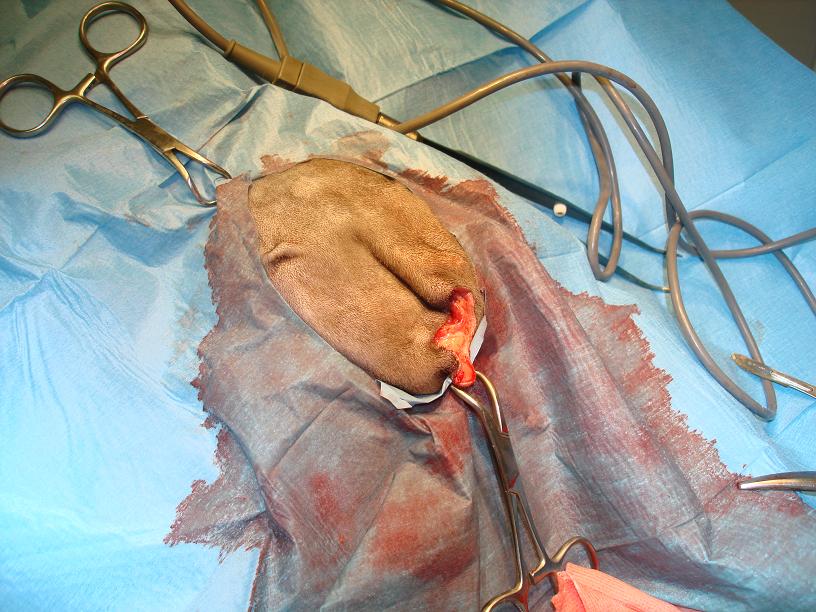

Na následující fotografii je vidět příprava kocoura na operaci. Černá šipka ukazuje místo počínající nekrotizace (odúmrtě) kůže.

Po přípravě operačního pole, jsme odpreparovali kůži a podkožní tkáně, až do oblasti dutiny vyplněné tekutinou: